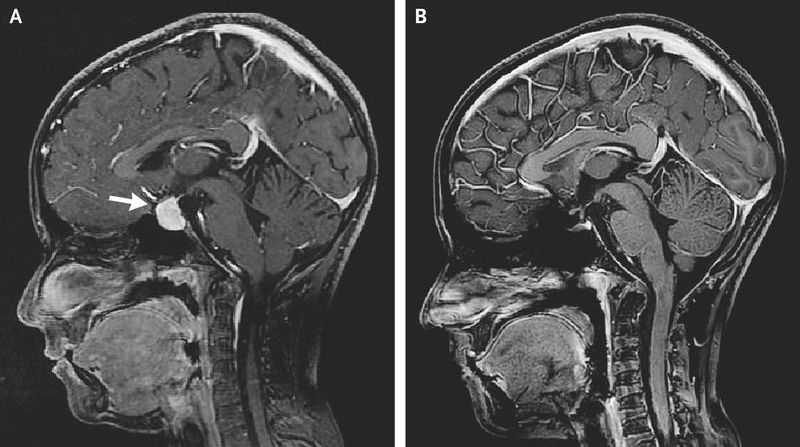

A 10-year-old girl presented to the pediatric clinic with headache and poor growth. On examination, her height was below the third percentile and her weight was at the tenth percentile. She had dry skin; testing showed no visual-field deficits. Laboratory studies showed a thyrotropin level of more than 150 μU per milliliter (normal range, 0.5 to 4.9), a free thyroxine level of 0.4 ng per deciliter (5.1 pmol per liter) (normal range, 0.8 to 1.4 ng per deciliter [10.3 to 18.0 pmol per liter]), and a prolactin level of 63 ng per milliliter (normal range, 3 to 28). The results of additional testing, which included the evaluation of levels of morning cortisol, gonadotropins, and insulin-like growth factor 1, were normal. Magnetic resonance imaging (MRI) of the head revealed a diffusely enhancing lesion in the sellar region extending to the optic chiasm (Panel A, arrow). A diagnosis of primary hypothyroidism with secondary pituitary hyperplasia was made, and the patient began receiving levothyroxine. Long-standing untreated primary hypothyroidism can cause pituitary hyperplasia owing to hormonal-feedback mechanisms through the hypothalamic–pituitary–thyroid axis. At 10 months of follow-up, the patient’s headaches had resolved, the thyrotropin level had normalized, and the patient had grown 6 cm in height. Repeated MRI of the head showed resolution of the pituitary enlargement (Panel B).